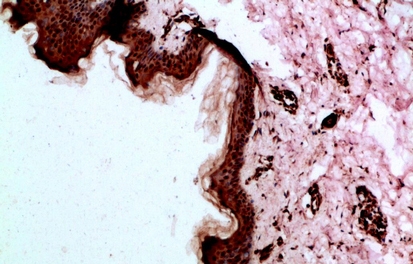

(Immunohistochemistry of paraffin-embedded Human skin tissue using Dsg1 Polyclonal Antibody at dilution of 1:200.)